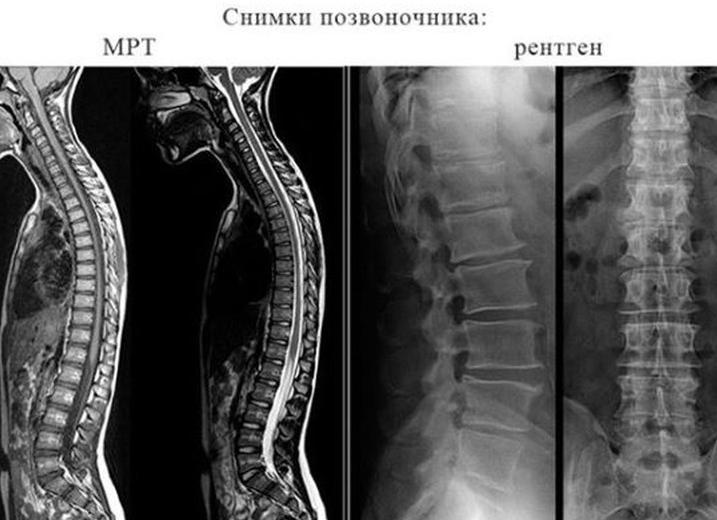

Что лучше – рентген или МРТ позвоночника

Комплекс предлагаемых современной медициной способов исследования включает в себя различные варианты рентгенологического исследования и магнитно-резонансную томографию (МРТ). Для того чтобы получить ответ на вопрос, что лучше рентген или МРТ позвоночника, необходимо произвести комплексную оценку эффективности предлагаемых методов лучевой диагностики.

Несмотря на то что конечный результат обследования с помощью МРТ или рентгена можно получить на снимке или в виде видеозаписи, принципы действия этих методов имеют существенные различия. В чем разница и почему при проведении обследования, предпочтение отдается тому или иному методу, можно разобраться, изучив физические основы, лежащие в основе рентгенологического и МРТ исследований.

Конечная интенсивность прошедшего сквозь тело пучка регистрируется на фотобумаге или с помощью цифровой техники. Таким образом, на полученном снимке отражаются проекции органов, о строении и внутренней структуре которых, можно судить по степени затемнения изображения. Костная ткань, в том числе позвоночник, имея чрезвычайно плотную структуру, практически не пропускает электромагнитное излучение и на снимках выглядит светлым пятном.

Если представить пучок электромагнитных волн, излучаемых рентгеновской установкой в виде мощного пучка света, то проекция костей будет «тенью». При использовании рентгена для диагностики патологий позвоночника, можно увидеть лишь «тень», или, другими словами, внешний контур костной структуры. С помощью рентгенографического исследования можно судить исключительно о внешних анатомических изменениях, происходящих в костной ткани позвоночника и околопозвоночных структурах.

Концентрация водорода позволяет судить о плотности структур и в соответствии с исследуемой областью позволяет получить изображение всех внутренних органов. В отличие от рентгена, МР-сигнал не проецирует контур костной составляющей, а передает изображение преимущественно мягких тканей, находящихся внутри (спинной мозг, позвоночный канал) и вокруг позвоночника.

Контраст между богатыми ионами водорода околопозвоночными тканями и низким содержанием водорода в костях, позволяет получить подробное изображение всех структур позвоночного столба. С помощью МРТ можно получить обзорный снимок всего позвоночника.